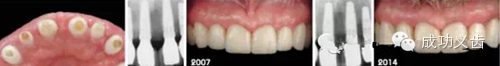

图1.延期种植1,2007年种植修复刚刚完成时的照片。

图2.延期种植2,2014年不论是从照片还是X线上,都显示出种植周围软硬组织稳定,颜色粉嫩!